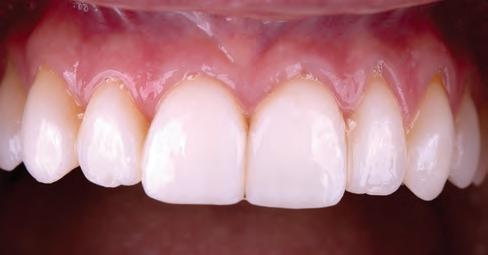

A 31-year-old woman presented with cosmetic concerns regarding her smile and requested a conservative enhancement. After clinical and radiographic analysis, digital 35mm photographs were taken and reviewed by the restorative clinician, technician, and surgeon (Fig 1). A digital impression was taken of the maxillary and mandibular arches using an intraoral scanner (Trios 3, 3Shape; Fig 2), and a smile design was developed with NemoSmile Design 3D software (Nemotec; Fig 3a). This allows for a facially driven smile frame to be created using reference lines of facial and smile proportions and natural teeth shapes and textures from the digital library (Fig 3b).

After developing the simulated mock-up, a 3D-printed resin model was created using CAD software (Fig 4a), and a clear PVS matrix (Exaclear, GC America) was fabricated to replicate the printed diagnostic wax-up using a nonperforated tray (Fig

Fig 1 Preoperative clinical views of a 31-year-old woman presenting with diastemas and limited tooth visibility. (top) Portrait. (center row) Intraoral views. (bottom row) Smile.

4b). This matrix was used to create an intraoral motivational mock-up with bis-acryl composite (Luxatemp Ultra, DMG). This additive mock-up provides the interdisciplinary team with an intraoral translation for evaluation (Fig 5). Upon evaluation of the digital smile frame and the clinical translation, it was determined that multiple esthetic and restorative requirements were necessary for an optimal biologic framework, and the interdisciplinary team determined the best sequence for these procedures. The patient was presented with the interdisciplinary treatment possibilities that included restoring the maxillary anterior teeth and premolars with a minimally

invasive preparationless procedure or with less conservative veneer preparations. The restorative materials discussed included injectable resin composites and ceramic (ie, feldspathic, pressable, machinable). For an optimal biologic framework and health, it was determined that connective tissue grafting would be necessary for treatment of the recessiontype defects on the maxillary left central and lateral incisors, canine, and premolars. The patient opted for the conservative preparationless composite veneers using the injectable resin technique followed by a connective tissue surgical procedure using the tunneling technique.